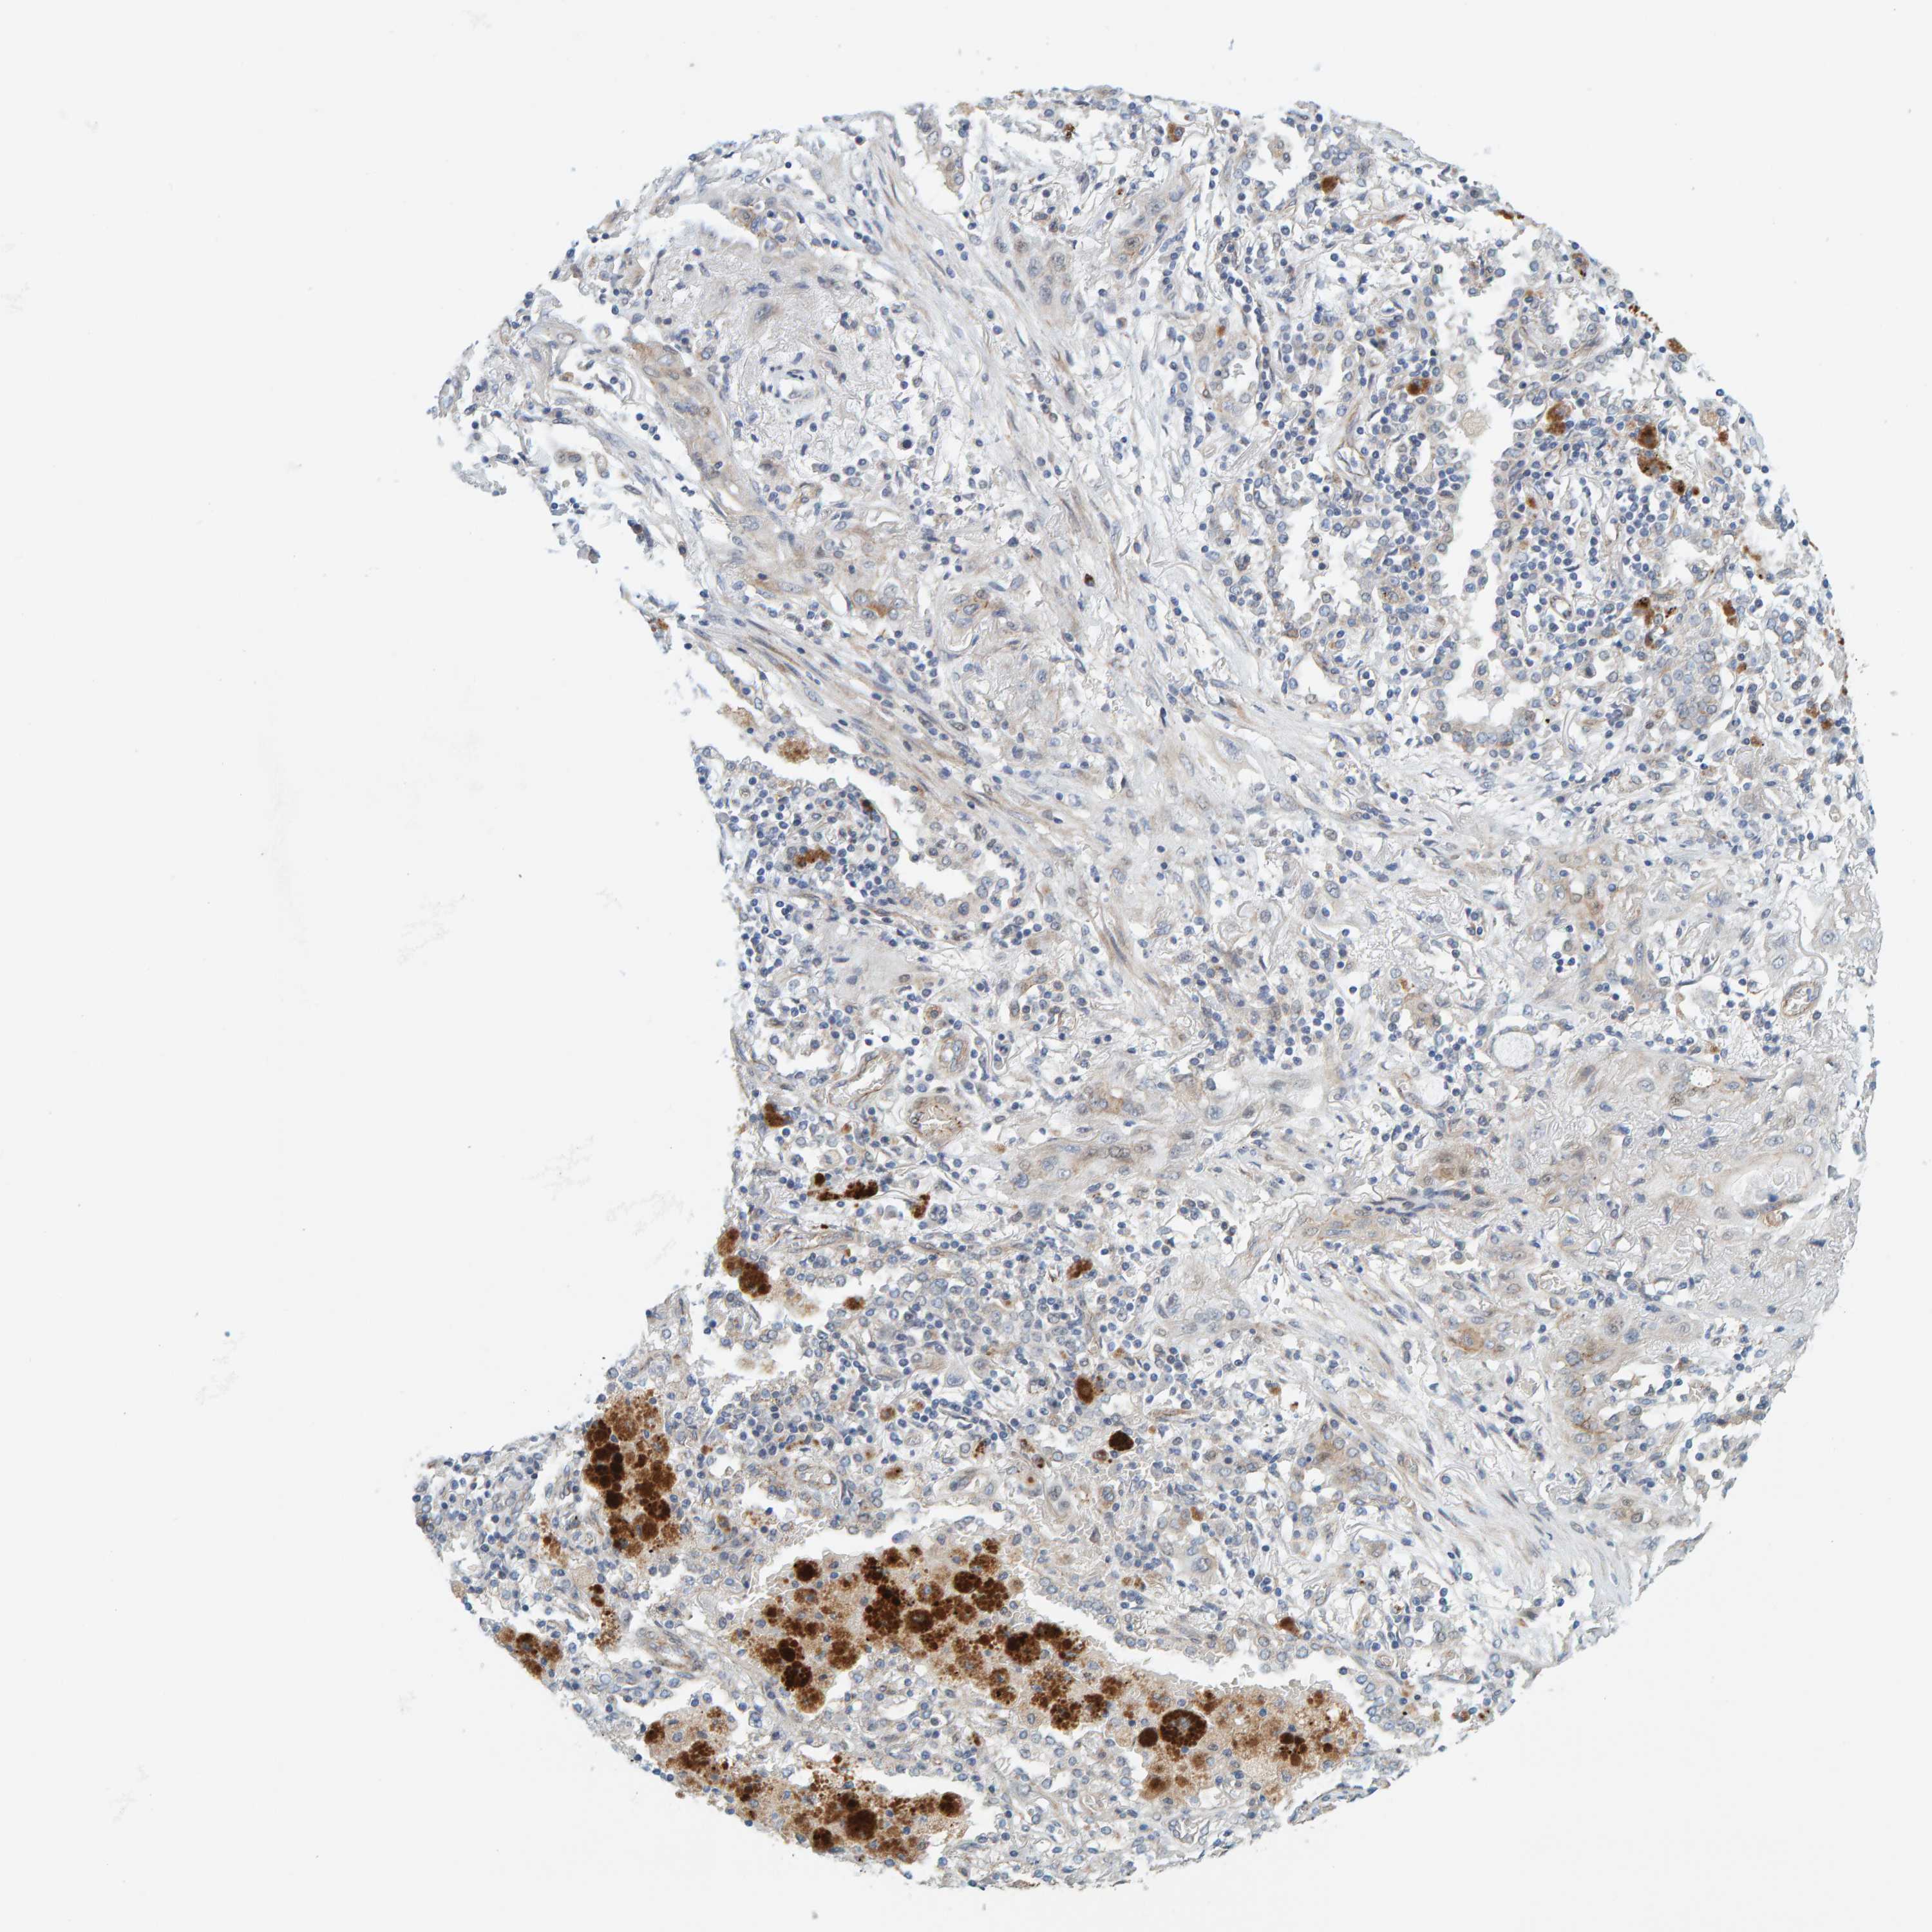

CANCER LUNG CANCER Show tissue menu

LUAD TCGA LUAD VALIDATION LUSC TCGA LUSC VALIDATION PROTEIN LUAD CPTAC PROTEIN LUSC CPTAC PROTEIN EXPRESSION

ANTIBODIES

AND

VALIDATION